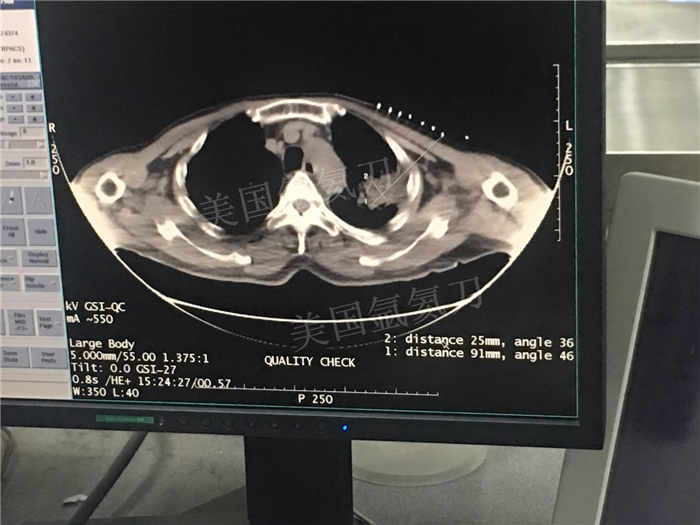

发布人:美国氩氦刀技术官方网站 发布时间:2018/7/5 10:57:23

下一篇:中日友好医院氩氦刀冷冻消融治疗胸膜间皮瘤